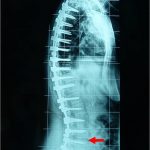

Οι συχνότερες παραμορφώσεις της σπονδυλικής στήλης είναι η σκολίωση και η κύφωση. Όταν αυτές ξεπερνούν τις 40°-45°, η χειρουργική αντιμετώπιση δίνει πολύ καλά αποτελέσματα, όπως μόνιμη και σχεδόν πλήρη διόρθωση της σκολίωσης και της κύφωσης.

Προεγχειρηρτικές και μετεγχειρητικές ακτινογραφίες σπονδυλικής στήλης ασθενούς με σκολίωση και κύφωση. Χάρις στη χρήση του συστήματος O-Arm επετεύχθει με ακρίβεια και ασφάλεια η τοποθέτηση των υλικών της σπονδυλοδεσίας.